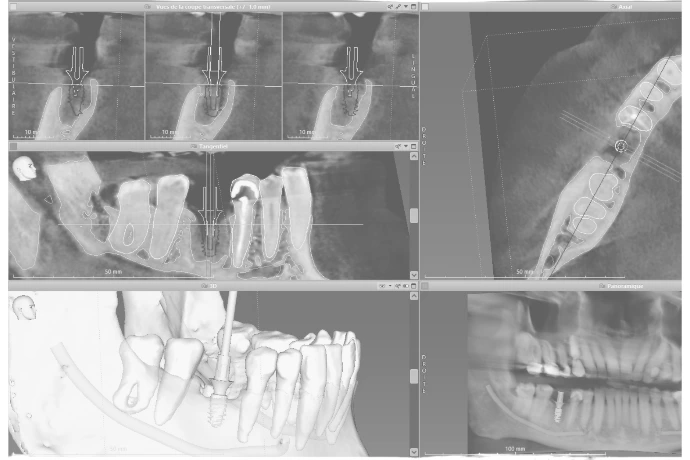

Introduction théorique, anatomie, planification et protocoles chirurgicaux.

Planification implantaire, chirurgie en direct, stratégies thérapeutiques, accastillage prothétique.

Travaux pratiques : planification (CoDiagnostix) - pose d’implants à main levée et guidée sur différents designs.